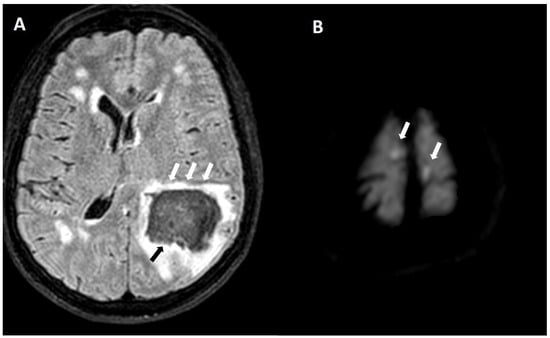

5.1.1. Lobar Hemorrhages

5.1.3. Convexity Subarachnoid Hemorrhage

5.1.4. Cortical Superficial Siderosis

6.1. Finger-like Projections

6.2. Subarachnoid Extension of Lobar Hemorrhage

6.3. DWI Lesions